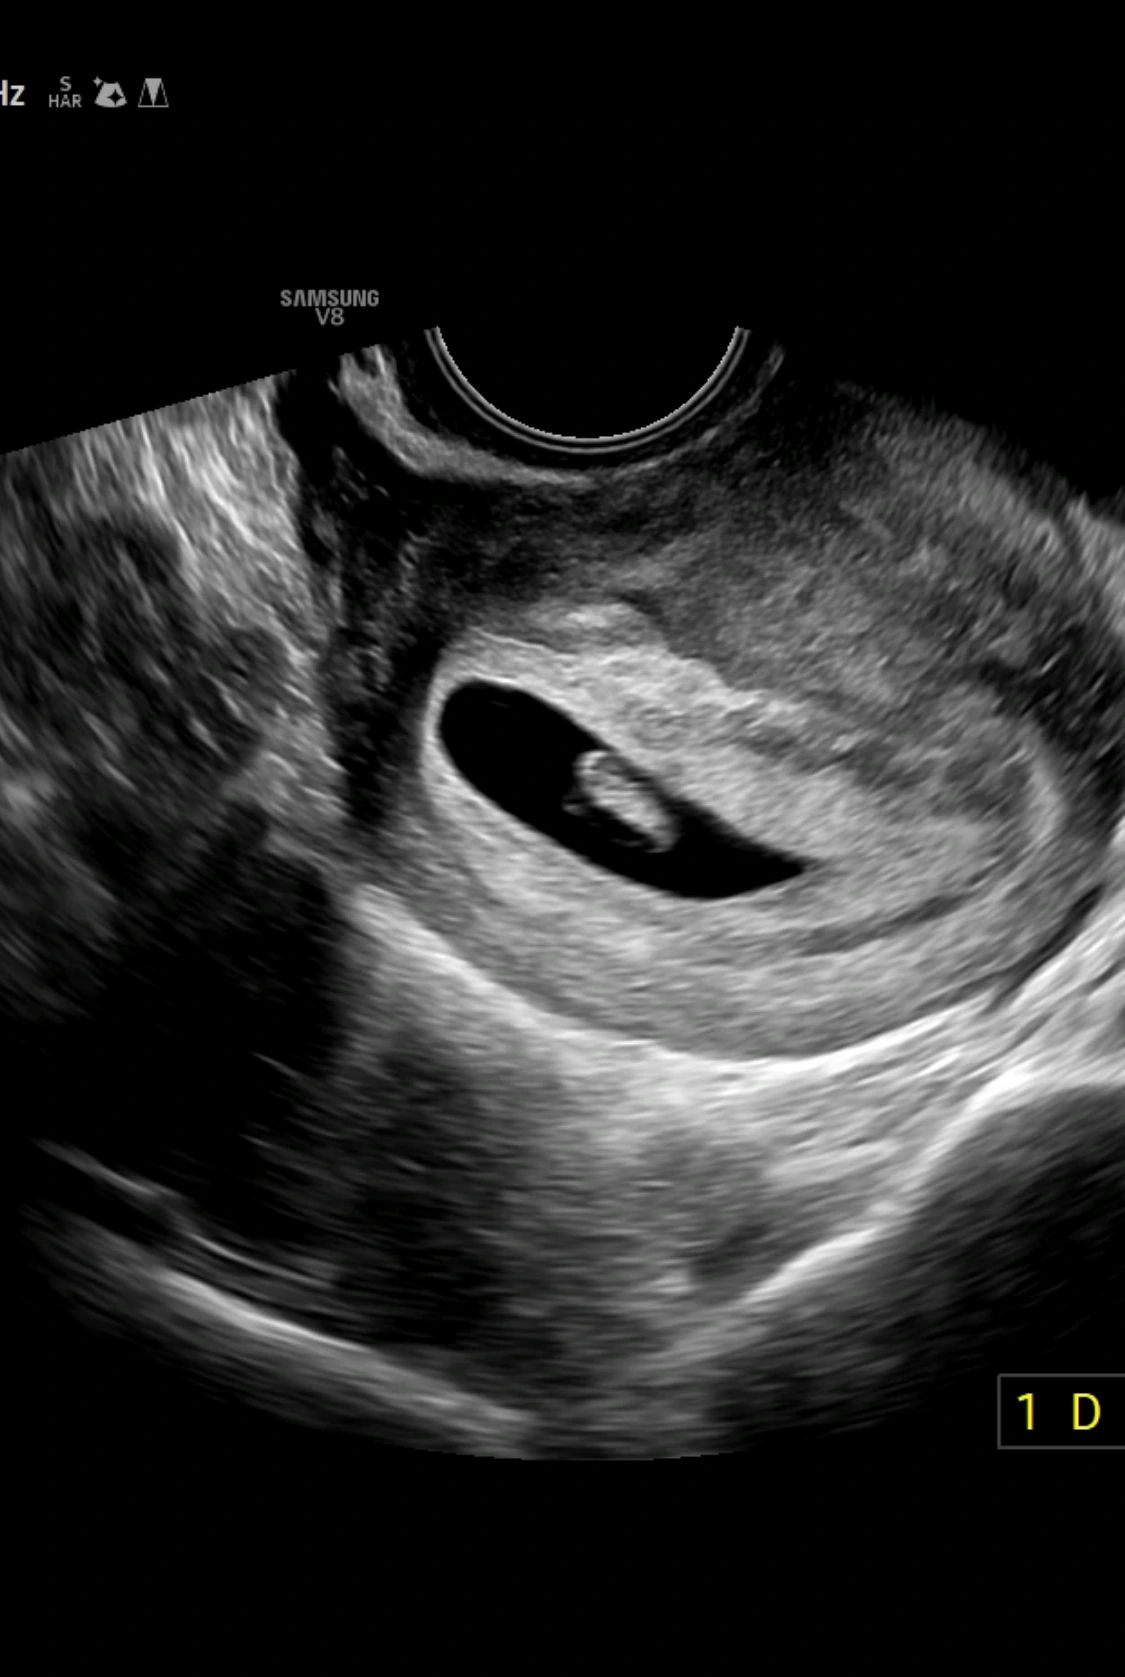

6주 6일 0.8cm 아기와 우렁찬 심장소리를 들었다.

일주일 뒤에 만난 아기는 그새 커져있었다. 이제 제법? 사람 모습이 될 준비를 하고 있었다.

오른쪽 아래 뾰족한 부분이 발이 된다고 한다. 나는 매일 토하고 우울하고 힘들었는데,

내 몸속에서 자라고 있는 아기는 잘 컸구나.. 신기하면서도 앞으로 몸이 얼마나 힘들어질까

걱정이 된다. 입덧약도 처방받았다. 2주 뒤에 만나자.